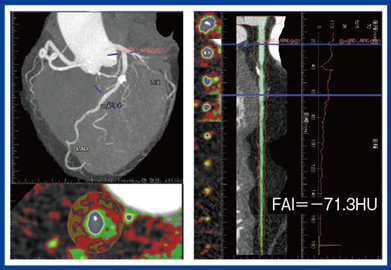

そして,最近注目されているのがCTによる冠動脈周囲脂肪の評価(Fat Attenuation Index:FAI)である。血管周囲の脂肪組織の炎症が,動脈硬化や不安定プラークの形成に影響があることが示唆されている。FAIは冠動脈周囲の脂肪組織濃度を示す指標で,炎症があるとFAIが高くなる。FAIでは,冠動脈疾患患者のリスク層別化が可能だと言われており,さらにプラークの性状評価とは独立した危険因子となる。すなわちFAIはプラークの性状にかかわらず心血管イベントを予測でき,冠動脈疾患の新たなリスクマーカーとなることが期待される。われわれは,FAIと冠動脈イベント発生との関連性についてメタ解析を行った2)。メタ解析は,過去の複数の観察研究を統合して,さらに高いエビデンスのデータを出す解析手法だが,その結果,FAIは心血管イベントと高い相関関係を示し,右冠動脈,左冠動脈前下行枝での評価が有用であると考えられた。FAIは,Ziostation REVORASにも搭載されており,FAIの評価が簡便にストレスなく可能となっている(図2)。

図2 Ziostation REVORASのFat Attenuation Index(FAI)